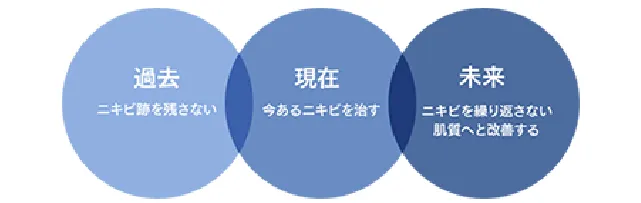

タカミクリニック ニキビ治療院では、ニキビを「きれいに治す」ことにこだわりを持ち、今あるニキビを治すだけでなく、ニキビ跡を残さない、ニキビができにくい肌質へ改善する治療を同時に行っております。美容医療でも改善に時間がかかるニキビ跡を残さないためにも、ニキビ治療の段階から、ニキビ跡を見据えた治療を行うことが必要です。ニキビ治療院では、豊富なニキビ治療の実績を持つ医師が治療を担当します。

- タカミクリニック式ニキビ治療でアプローチする3つの時間軸